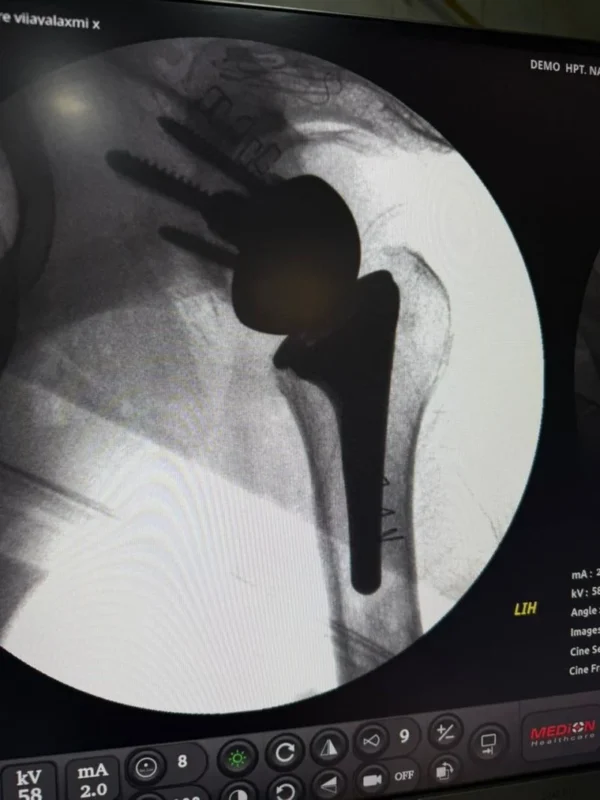

We recently managed an 81-year-old gentleman with severe Hemophilia B (FIX <1%, inhibitor negative) — possibly among the oldest patients to successfully undergo major orthopedic surgery in this setting.

Indication: Left gleno-humeral joint osteoarthritis secondary to recurrent hemarthrosis

Procedures: Left shoulder joint replacement plus prostate surgery

With meticulous perioperative planning, we administered a single pre-operative dose of Refixia (80 IU/kg; 4000 IU) 1–2 hours prior to incision.

- Surgery was completed successfully

- No intraoperative or postoperative bleeding complications

- No additional factor dosing required

- Post-operative course remained stable

- Inhibitor screening remained negative

This case highlights the power of extended half-life Factor IX in enabling safe major surgeries with reduced dosing burden — even in elderly hemophilia patients with advanced joint disease.